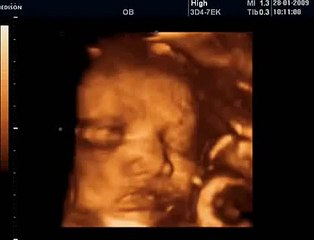

18 Haftalık Gebelik Bebek Ultrason Görüntüsü

Hafta hafta gebelik dönemi 18 haftalık bebek ultrason görüntüsü. Gebelikte 18. hafta daha çok bilgi için sayfamızı ziyaret edebilirsiniz.